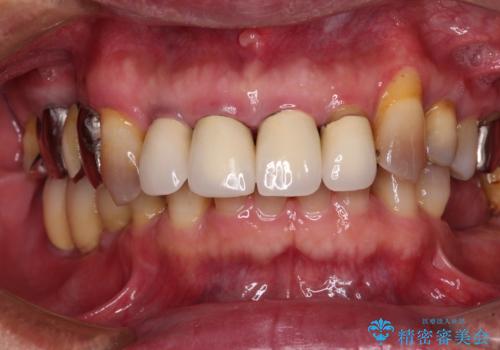

[ 虫歯・歯周病・インプラント ] 全顎補綴治療

![[ 虫歯・歯周病・インプラント ] 全顎補綴治療の症例 治療前](https://seimitsushinbi.jp/wp/wp-content/uploads/2025/08/70fb1789aa801a8616f6634871c40673-500x350.jpg?v=1754470286)